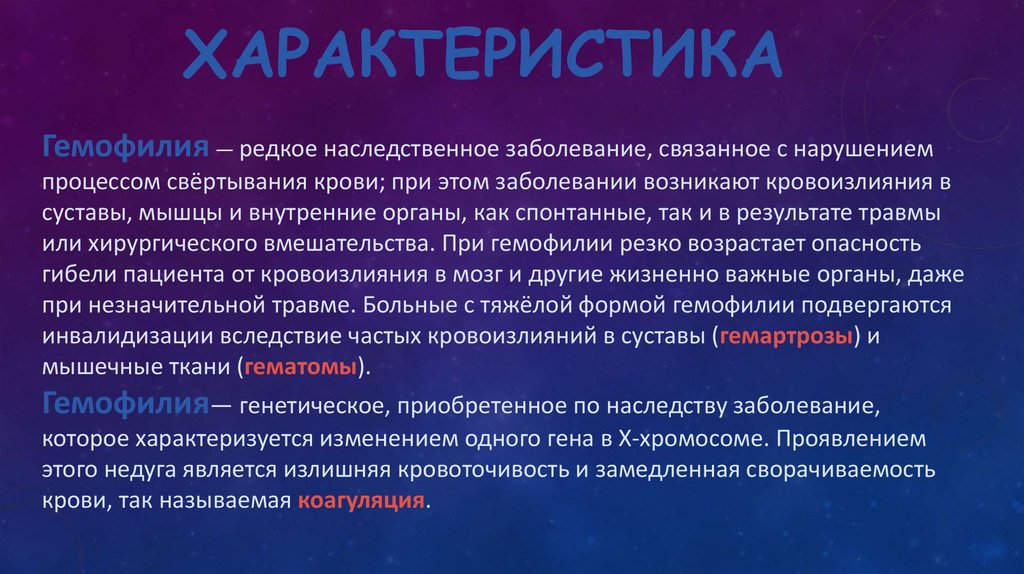

Генетика гемофилии: рецессивные гены и их проявления